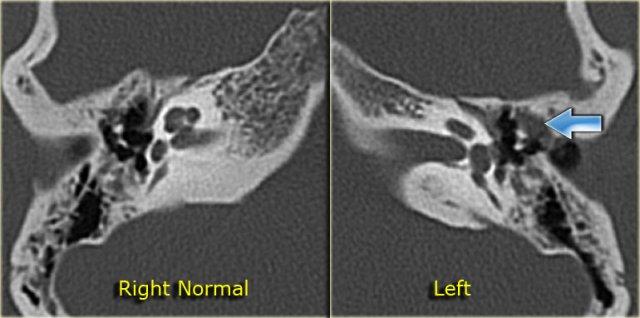

Dị dạng ống bán khuyên ngoài

Các dị dạng của tiền đình và ống bán khuyên có thể thay đổi từ một khoang chung cho tất cả các cấu trúc này đến ống bán khuyên ngoài kém phát triển.

Trong quá trình phôi thai học, ống bán khuyên ngoài là cấu trúc hình thành cuối cùng, do đó trong các dị dạng của ống bán khuyên, ống ngoài thường bị ảnh hưởng nhiều nhất.

Bên trái là hình ảnh của một bé trai 10 tuổi, được lên kế hoạch cấy ốc tai điện tử.

Có sự giãn rộng và ngắn lại của ống bán khuyên ngoài.

Tiền đình tương đối lớn (mũi tên).

Bên trái là hình ảnh của một bé trai 16 tuổi, được khám tiền phẫu vì cholesteatoma tai phải.

Là một phát hiện tình cờ, có hình ảnh ống bán khuyên ngoài phình to (mũi tên vàng) và vắng mặt ống bán khuyên trên (mũi tên xanh dương).

Tại vị trí dự kiến của ống bán khuyên trên chỉ quan sát thấy một gờ nhỏ.

Ống bán khuyên sau bình thường.